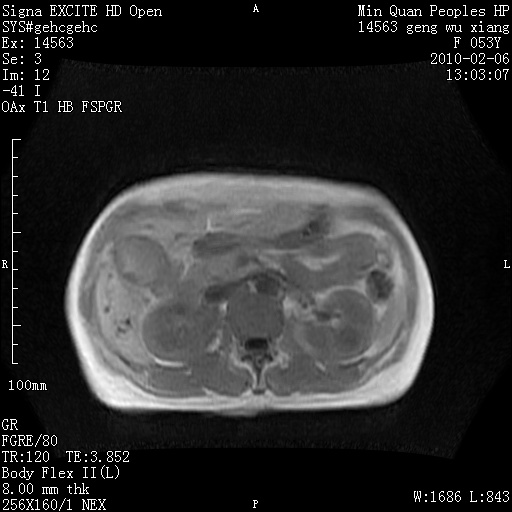

标题: MRI2762:胆道梗阻原因?

f,53y,全身黄染多日。

高位胆道梗阻 胆管癌可能性大

支持 高位胆道梗阻 胆管癌可能性大。